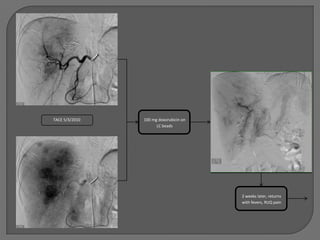

TACE 5/3/2010   100 mg doxorubicin on

LC beads

2 weeks later, returns

with fevers, RUQ pain

CT 5/19/2010: near- complete

tumor necrosis

Prolonged     CT 8/6/2010: Biloma

Percutaneous biloma         catheter         resolved, but

drainage              drainage   intrahepatic recurrence

and new lung nodule.

To study drug